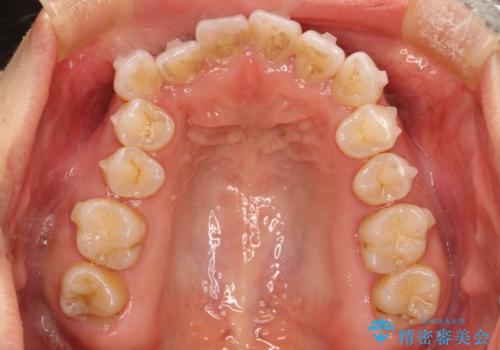

抜歯せずに八重歯のマウスピース矯正

- 非抜歯・遠心移動+IPR+拡大 によるマウスピース矯正を計画した。

八重歯がシビアな場合、抜歯をしないと治せないケースもありますが、奥歯の位置関係を修正したり、歯のサイズダウンを行うことで、抜歯をせずに改善できる場合もたくさんあります。